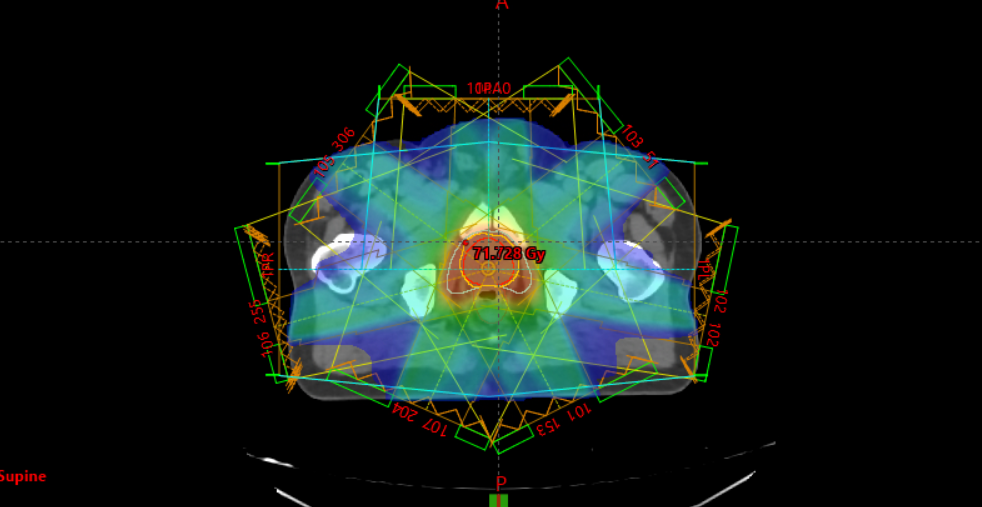

The planning process for radiation therapy is complex. It involves producing optimum dose distribution that will destroy the tumour, while sparing as much healthy tissue as possible.

The planning process is a combined effort between the oncologist, radiographers, physicist as it requires clinical knowledge and technical expertise to achieve the best possible outcome for the patient.

The next step is a CT simulation to produce a scan from which the radiation team will plan the angles and shapes of radiation beams. Imaging scans will be taken to assist Dr Smalberger in pinpointing the exact treatment area to target during radiation. Once the CT simulation is done, it will take a few days to plan the treatment.